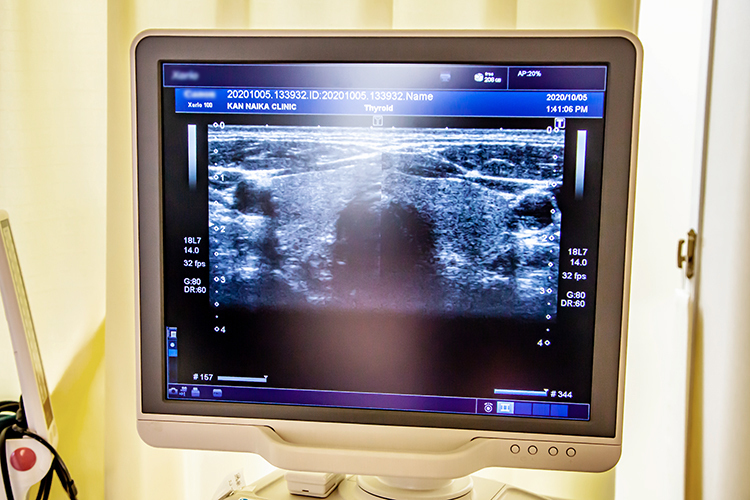

▲甲状腺疾患の治療のための設備が充実

血液検査と超音波検査を行います。血液検査では、甲状腺ホルモンの量と甲状腺を刺激する物質の量を測定します。ただし、血中に甲状腺ホルモンの量が多いというだけで、すぐに甲状腺疾患と診断はできません。甲状腺はホルモンの製造と貯蔵を担う臓器です。血中ホルモン量が多い場合には、製造過多のほか貯蔵庫から漏れたものが血液中に入り込んでいる可能性もあるので、専門的な知識を持った医師の診断が必要となります。一方、超音波検査では、甲状腺の腫れや内部の血流の状態などをチェックします。当院の場合、血液検査の結果が1時間ほどでわかります。このため、検査をした日に診断して、治療が必要な場合は即日スタートが可能です。

▲実際に甲状腺を撮ってそれを見ながら説明してくれる